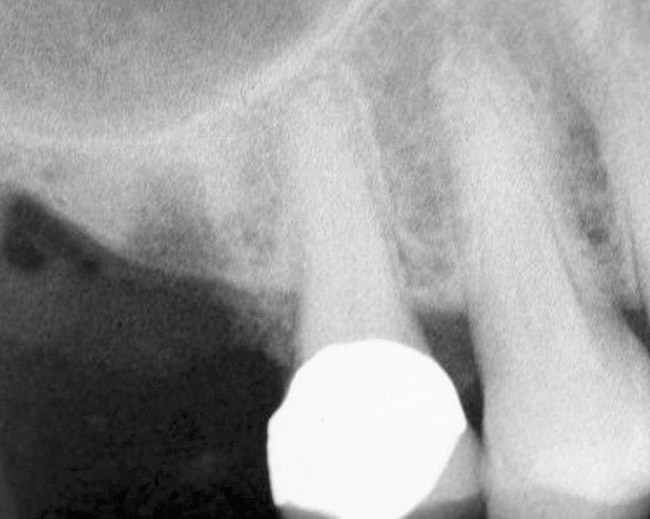

Figure 11  Insertion of a 4.8-mm implant, which fit snugly and increased the surface area for future osseointegration

Figure 11

If the final osteotome employed was 3.5 mm, the size of the implant that can be placed should be 4.1-mm diameter or larger depending on the width of the ridge. Several factors should be considered when selecting the width of the inserted implant. If the height is relatively short (eg, 8 mm), a wider implant such as a 4.8-mm diameter will provide 30% more surface area than a 4.1-mm diameter implant (Figure 5).24 In addition, the wider implant will provide additional stability, especially if hand use of osteotomes caused some irregularities of the osteotomy site.

Figure 5  Insertion of a 4.8-mm implant, which fit snugly and increased the surface area for future osseointegration.

Figure 5